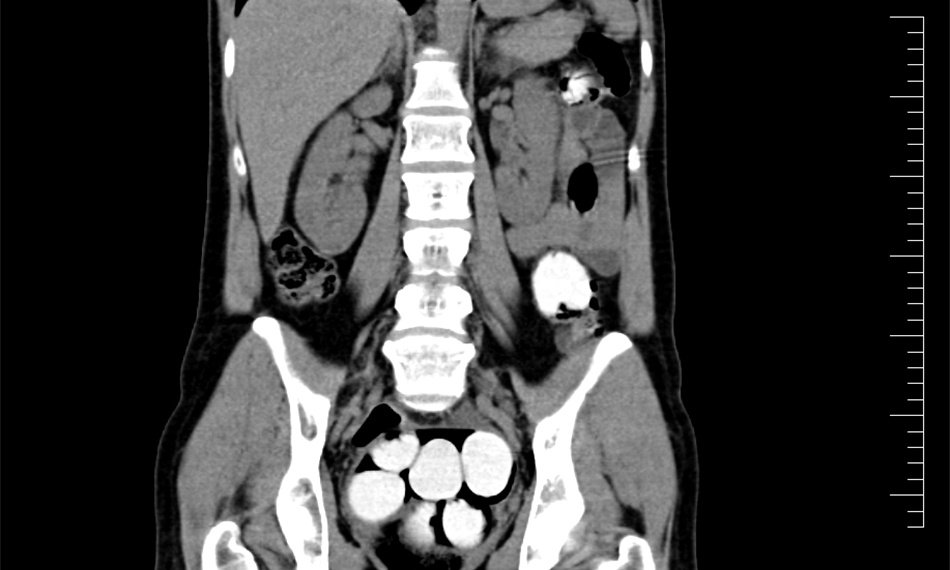

Ke kontrole byl polykač celníky vytipován na základě provedené rizikové analýzy daného letu. Prvotní podezření na pašování drog celníkům potvrdily kontrolní stěry DrugWipe z rukou pašeráka s pozitivní reakcí. Při důkladné kontrole jeho zavazadel a osobní prohlídce nebyly drogy nalezeny, proto bylo provedeno následné CT vyšetření v nemocničním zařízení, které podezření potvrdilo.

Postupně z těla pašeráka vyšlo 124 kontejnerků naplněných bílým práškem. Chemická látka při provedení detekční zkoušky NARK II pozitivně reagovala jako kokain. Celková hmotnost všech kapslí je 1 429,1 g. Určení vlastní hmotnosti a druhu zajištěné drogy je předmětem další odborné expertízy. Podle zkušeností celníků se s největší pravděpodobností jedná o velmi koncentrovaný kokain. Zda byla droga určena na český trh nebo k distribuci v jiné zemi, je předmětem dalšího šetření.